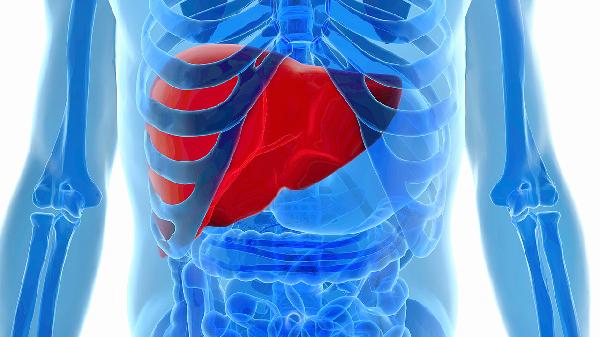

脂肪肝可通過超聲檢查、肝功能檢測、癥狀觀察、風(fēng)險(xiǎn)評估、影像學(xué)確認(rèn)等方式診斷。脂肪肝通常由肥胖、酒精攝入、代謝異常、藥物副作用、病毒性肝炎等原因引起。

腹部超聲是診斷脂肪肝的首選方法,能清晰顯示肝臟脂肪浸潤程度。超聲下脂肪肝表現(xiàn)為肝臟回聲增強(qiáng)、遠(yuǎn)場衰減,與正常肝組織對比明顯。輕度脂肪肝可能僅需定期復(fù)查,中重度需結(jié)合其他檢查進(jìn)一步評估。

早期脂肪肝多無癥狀,部分患者出現(xiàn)右上腹隱痛、乏力、食欲減退。進(jìn)展期可能伴隨肝區(qū)壓痛、蜘蛛痣等體征,非酒精性脂肪肝患者常合并代謝綜合征表現(xiàn)如腰圍增粗。

CT檢查可量化肝臟脂肪含量,MRI-PDFF技術(shù)能精確評估脂肪變性程度。影像學(xué)檢查適用于超聲診斷不明確或疑似進(jìn)展為脂肪性肝炎的病例,可發(fā)現(xiàn)肝纖維化早期改變。